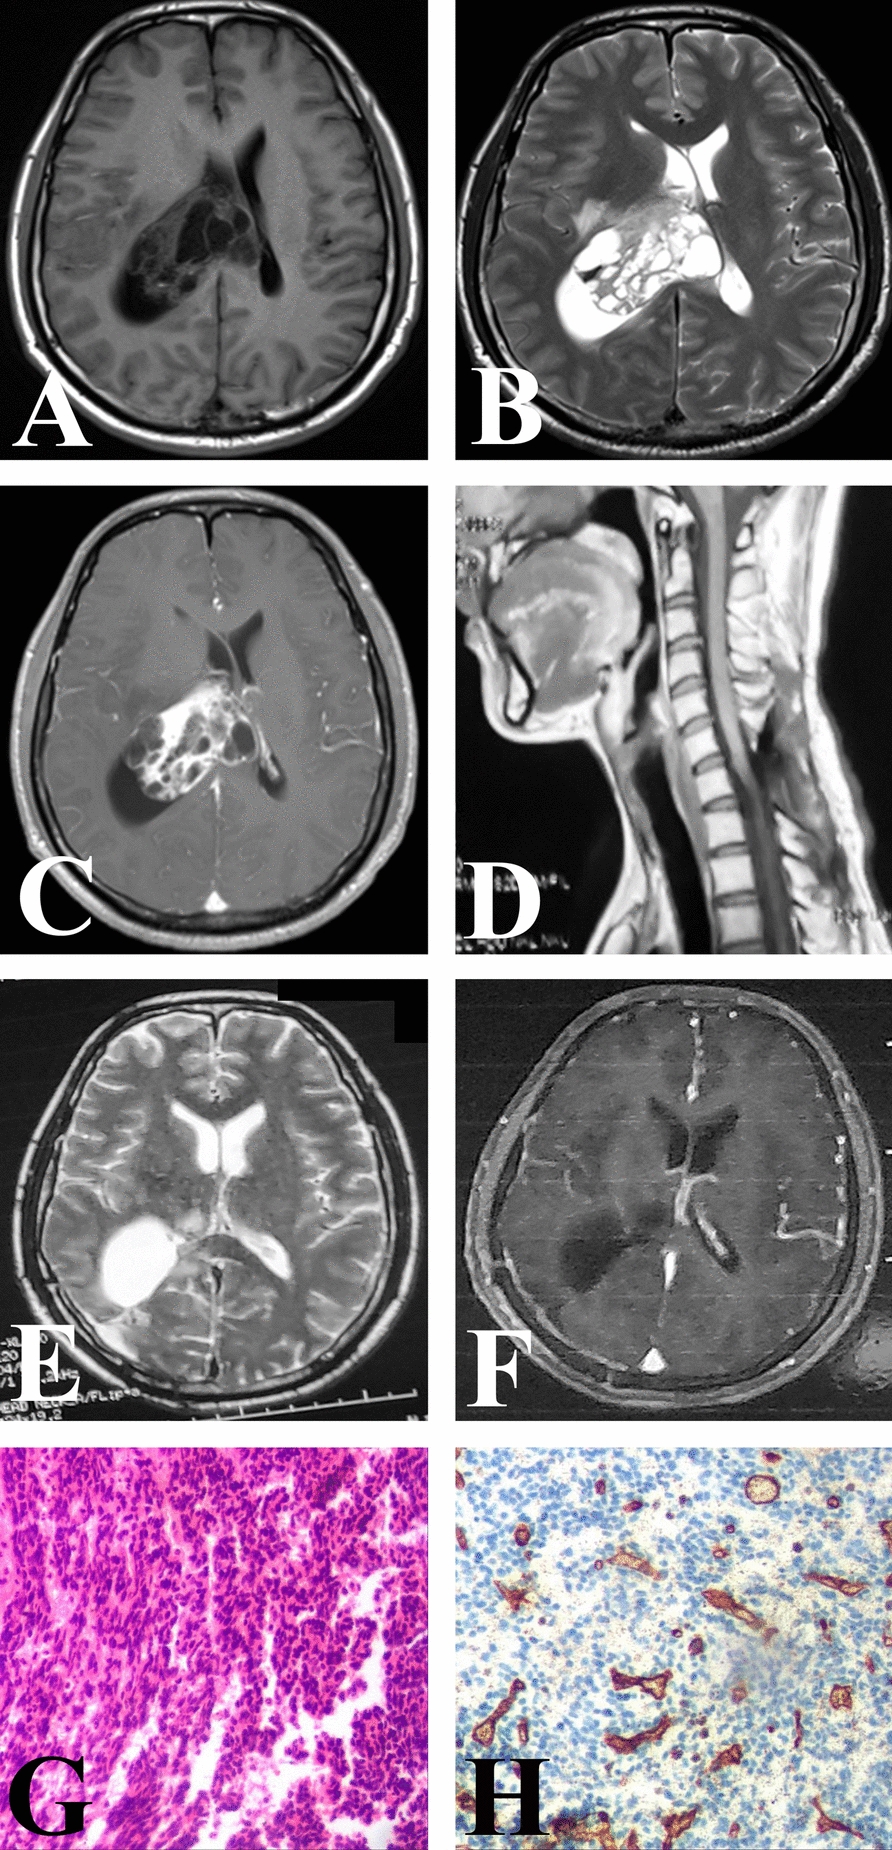

Case presentation: A 32-year-old male patient of Chinese ethnicity was diagnosed with a grade 2 intraspinal solitary fibrous tumor, demonstrating metastatic spread to the trigone region of the lateral ventricle. Despite cystic degeneration, the solid component of the metastatic lesion exhibited signal intensity similar to that of the primary tumor on imaging. A piecemeal gross total resection was achieved, and postoperative immunohistochemical analysis confirmed that the metastatic lesion was categorized as grade 3, with an increase in the Ki-67 proliferation index from 20% to 30%. Both the primary and metastatic tumors exhibited negative expression of CD34. Although radiotherapy was considered, consensus on its use was not reached, and the patient succumbed to tumor progression 17 months later.